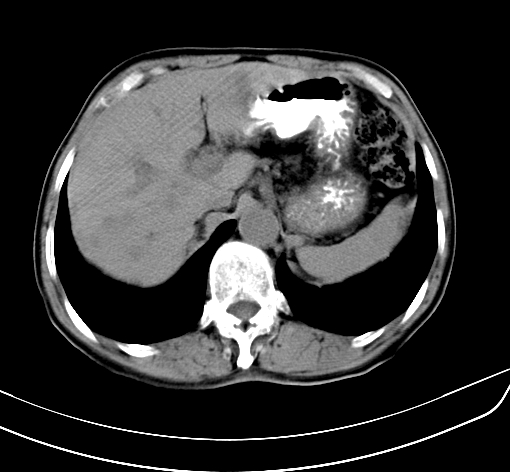

病人 男 70 咳嗽 胃部不适 2月余

1、考虑肝门占位,肝内胆管扩张,建议强化  2胆囊区胆囊显示不佳邻近肝组织内见低密度区是否考虑胆囊癌侵犯肝脏

胆囊壁增厚,与临近肝实质边界不清,临近肝实质内可见大片边界不清之低密度区,肝门区密度亦有减低,部分结构不清,尾叶前方可见块状影,肝右叶可见多枚边界不清之圆形低密度区,肝内胆管扩张征象,结合病史考虑1胆囊癌肝内转移,肝门区淋巴结转移,门脉癌栓待排2肝内胆管扩张3建议增强扫描

肝脏多发大小不等低密度灶,边界不清,肝门区结构不清,肝内胆管轻度扩张,胆囊密度不均匀,内见软组织样密度影,与相临肝脏边界不清.考虑:1、胆囊ca侵犯肝脏并肝内多发转移,肺上也有结节影,转移?建议强化扫描.2、胃充盈不好,如怀疑有病变最好建议做相关检查.

胆囊壁增厚,周围模糊不清,肝内多发低密度影,胃充盈欠佳,胃壁增厚,外形尚规整,考虑胆囊炎、胆囊癌肝内转移?建议胃肠道进一步检查或增强扫描。